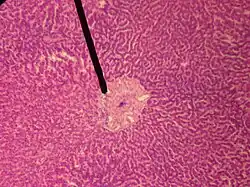

Central veins of liver

In microanatomy, the central veins of liver (or central venules)[1] are veins found at the center of hepatic lobules (one vein at each lobule center).

![]() human central vein | |

They receive the blood mixed in the liver sinusoids and return it to circulation via the hepatic veins.[2]

The circulation of venous blood is: portal vein (which is formed by the joining of the superior mesenteric vein with the splenic vein) drains into the sinusoids of the liver, these all drain into the central veins of liver which drain into the hepatic vein to be returned to IVC.